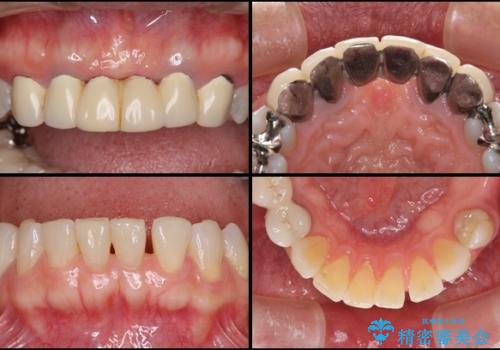

金属を使用した前歯のブリッジや奥歯の銀歯は全てオールセラミッククラウンまたはセラミックインレーとし、左下の奥歯はインプラントにより治療を行うこととしました。

外科処置を行うため、治癒を待つ期間が数ヶ月あるため、その期間を利用して下顎前歯のスペースを矯正治療で閉じることとしました。

遠方からの来院であったので、1回の治療時間を長めにし、できる限りの処置を集中して行うことで、来院回数を減らすことができました。

矯正治療までは考えていなかったそうですが、物が挟まっていた前歯のスペースがなくなり、矯正治療を行って良かったとのことでした。

初診カウンセリングを含めて13回の通院で治療を終えることができ、患者様には大変満足していただきました。